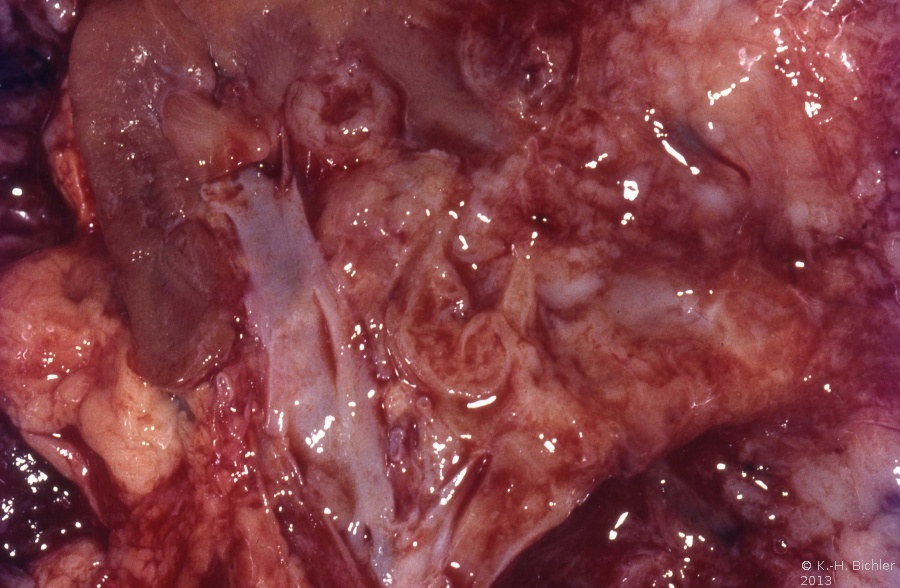

Die karzinomatöse Entartung persistierender metanephrogener Stammzellen (Blastem) auf der Grundlage einer zytogenetischen Deletion auf dem kurzen Arm des Chromosoms 11 in der p13-Region (Wilmstumor1-Gen) bzw. Mutation auf 11p15,5 (WT2-Gen) führen zur Entwicklung eines Wilmstumors. Durch die Pluripotenz des Blastems können vielfältige epitheliale und mesenchymale Zell- und Gewebskomponenten nebeneinander histologisch nachweisbar sein, wie beispielsweise alle in der Niere vorkommenden Gewebe, aber auch Skelettmuskel-, Knorpel- und Schleimzellen. Die Tumoren können zystisch aufgebaut sein. Anaplastische Tumoranteile (Kernhyperchromasie, hyperdiploide Mitosen, mehr als dreifach vergrößerte Zellkerne) treten in ca. 5% der Fälle auf und sind als prognostisch ungünstiges Kriterium zu werten. Die Tumorzellen können - genau wie beim Nierenzellkarzinom - durch Aggregation in den Blutgefäßen Tumorthromben bilden (Abbildung 1c). Wilmstumoren metastasieren nach medial in die Lymphknoten und hämatogen in die Lunge. Vereinzelt finden sich ZNS-, Leber- und Skelettmetastasen.